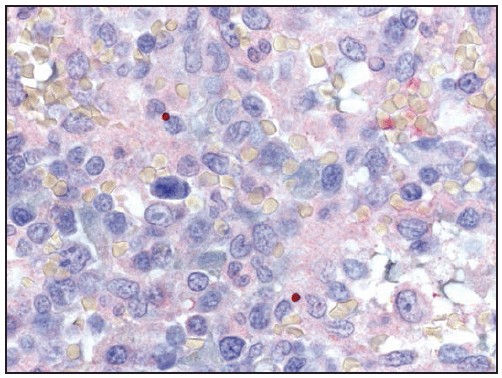

Ehrlichiae are obligate intracellular bacteria that infect peripheral blood leukocytes. E. chaffeensis, the pathogen that causes human monocytic ehrlichiosis, predominantly infects monocytes and tissue macrophages ( Figure 27). The organisms multiply in cytoplasmic membrane-bound vacuoles, forming tightly packed clusters of bacteria called morulae. In patients with fatal E. chaffeensis ehrlichiosis, systemic, multiorgan involvement has been described with the greatest distribution of bacteria in the spleen, lymph nodes, and bone marrow (128). Unlike in RMSF, direct vasculitis and endothelial injury are rare in ehrlichiosis. The host systemic inflammatory response, rather than direct effects of the pathogen, is likely to be largely responsible for many of the clinical manifestations of ehrlichiosis (129).